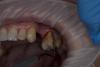

carloss Опубликовано 27 сентября, 2013 Поделиться Опубликовано 27 сентября, 2013 мне действительно хочется, не могли бы показать и указать на что обратить внимание. в общем как спланировать))Нужно чтобы корни были хотя бы средней длины, и выраженный без перегородок между корнями, что случается.. ещё желательно хорошо сохранившаяся дистальная и нёбный стенки, если есть и вестибулярная, то можно обойтись без вкладки.. срезать надо корень с прилегающей частью коронки, желательно, чтобы образовалась не очень вогнутая поверхность http://savepic.su/3393568.jpg http://savepic.su/3398688.jpg Ссылка на комментарий

Art 7 Опубликовано 27 сентября, 2013 Автор Поделиться Опубликовано 27 сентября, 2013 (изменено) там пломба объёмная но стенки думаю в полном поряде, и с длинной корней проблем нет вообще. теперь чисто практические вопросы если можно,?-отслаиваться вестибулярно надо?-прежде чем ампутировать надо очистить полость от пломбы чтобы визуализировать лучше? Изменено 27 сентября, 2013 пользователем Art 7 Ссылка на комментарий

carloss Опубликовано 27 сентября, 2013 Поделиться Опубликовано 27 сентября, 2013 там пломба объёмная но стенки думаю в полном поряде, и с длинной корней проблем нет вообще. теперь чисто практические вопросы если можно,?-отслаиваться вестибулярно надо?-прежде чем ампутировать надо очистить полость от пломбы чтобы визуализировать лучше?Отслаиваться вестибулярно, если только по по проекции ампутируемого корня, дистально лучше не провоцировать рецессии кости, может она там тонкая.. Полость желательно очистить, хотя можно срезать и с пломбой, сначала можно срезать поменьше, потом, при визуализации, можно доснять и хорошенько заполировать, обратите внимание, чтобы не осталось "заусенцев", а всё гладко переходило одно в другое.. лучше сразу временную коронку, которая прикрывает лунку корня 1 Ссылка на комментарий